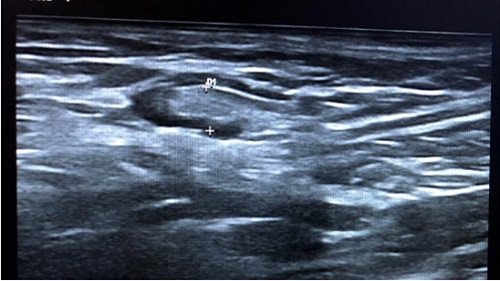

Niño de 3 años que acude por adenopatía cervical grande no dolorosa de semanas de evolución. Asintomático. Recibe tratamiento con amoxicilina-clavulánico durante dos semanas sin mejoría. En la exploración física: adenopatía de consistencia elástica, no móvil y no dolorosa. Se realiza ecografía objetivando adenopatía heterogénea con focos hipoecoicos (necrosis) con bordes irregulares, forma ovalada (Fig. 4) sin visualizar imagen Doppler central (Fig. 5), con artefactos en zonas periféricas. Se realiza Mantoux positivo y se deriva para estudio y exéresis quirúrgica diagnóstica y terapéutica. Se aísla Mycobacterium avium y recibe tratamiento con rifampicina.

Figura 4. Adenopatía heterogénea con focos hipoecoicos